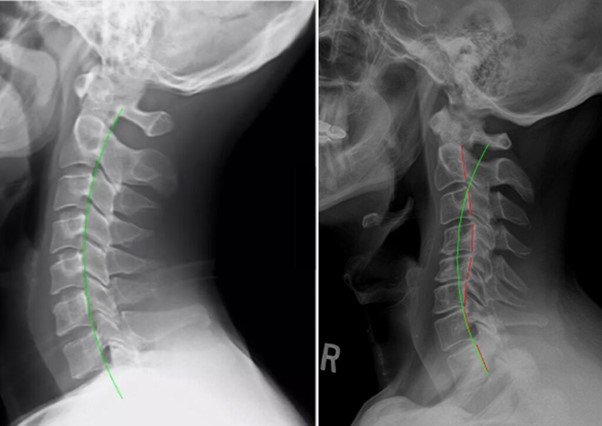

Cervical spine malalignment and loss of normal curvature as seen on the x-ray of a post whiplash injury patient